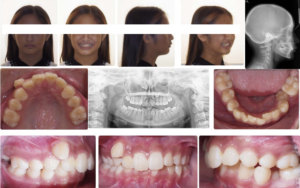

A 12 year old Asian female presents with a chief concern that “my teeth are crooked and I have a tooth stuck”